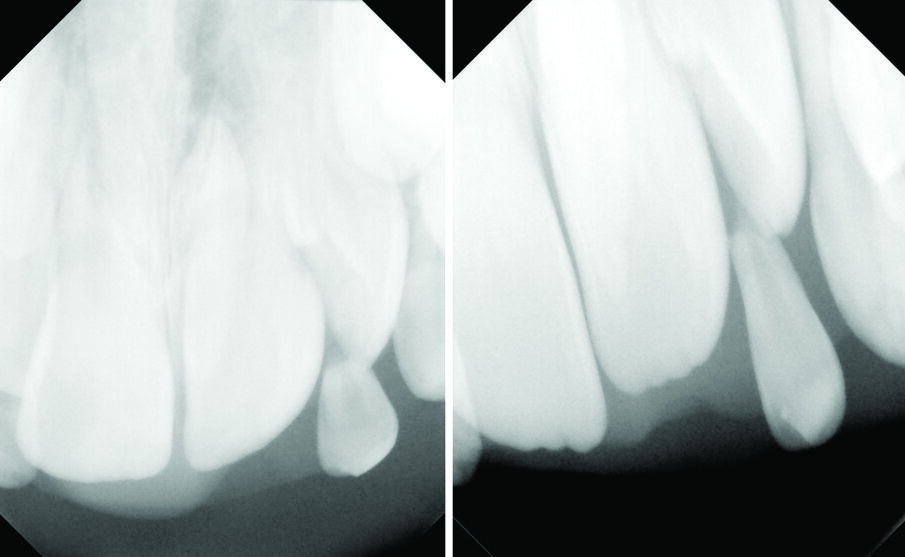

An eight and half year-old girl (LT) attended the paediatric dentistry department of Hamdan Bin Mohammed College of Dental Medicine (HBMCDM) in Dubai Healthcare City for an opinion. The patient’s mother was concerned about the delayed eruption of an upper front tooth (21) that was affecting her child’s appearance (Figs. 1 a, b & c). LT was medically fit and healthy with no history of previous dental trauma. She was in the mixed dentition stage. Tooth 11 had erupted 4 months ago in cross bite but 21 had not erupted yet. Its eruption was much delayed (usually erupts at 7 ½ years of age). Looking back at previous x-rays, a DPT was taken a year ago and it was noticed that an important feature was missed. Retrospectively, the presence of a supernumerary tooth ($) in the area of 21 and congenital missing 47 was confirmed (Fig. 2). Two new x-rays, namely upper intra oral periapicals and the parallax technique (distal shift) showed a supernumerary tooth (conical and inverted) in a palatal position (Figs. 3 a & b). LT also had dental caries of her primary teeth (Figs. 4 a & b), had a pronounced gag reflex and was dentally anxious.

Figs. 3 (a & b). Periapical xrays show the presence of an inverted conical supernumerary tooth present palatally to 21 (parallax).